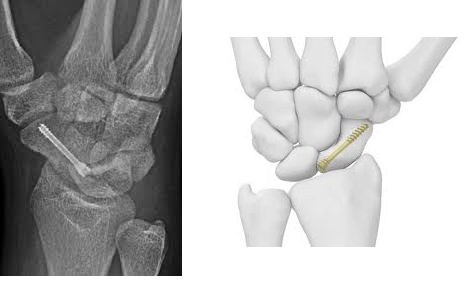

- Șuruburi sau plăci metalice: Utilizate pentru a stabiliza fractura, mai ales dacă este deplasată sau nu se vindecă corect.